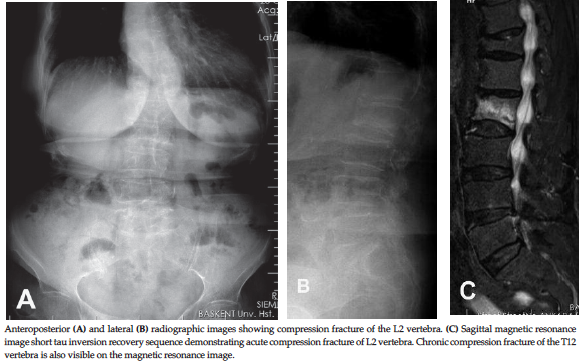

Figure 1. Preoperative Radiologic Images

diagnosis of acute VCF was established with magnetic resonance imaging (short

tau inversion recovery) sequences (Figure 1). Plain radiographic and computed

tomography scans were also used (Figure 1). All fractures were treated with